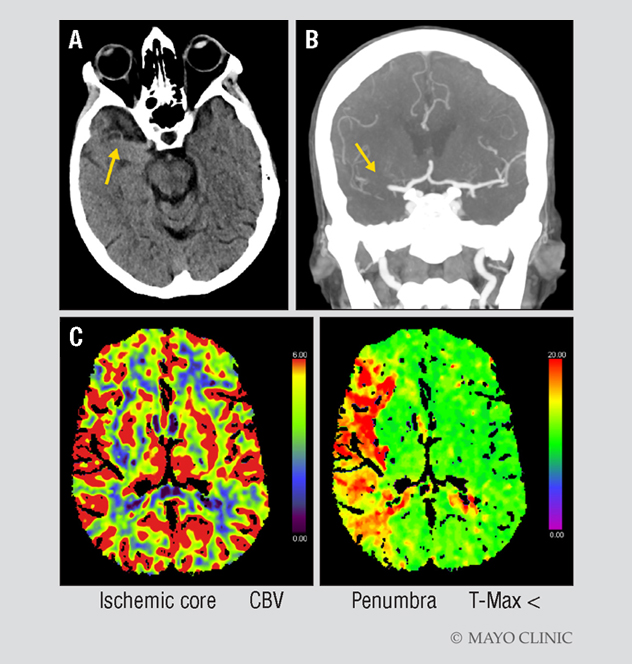

A. CT of a 70-year-old woman shows a hyperdense vessel sign (arrow), as well as a right gaze preference and no bleeding. The woman had presented at Mayo Clinic in Jacksonville, Florida, with acute left facial droop, left arm weakness and slurred speech. Her initial NIH Stroke Scale score was 17; her Alberta Stroke Program Early CT Score (ASPECTS) was 10. B. CT angiogram confirmed a right middle cerebral artery clot (arrow). C. CT perfusion imaging shows a large mismatch between ischemic core, indicated in red in the left-hand image, and penumbra, indicated in green in the right-hand image.